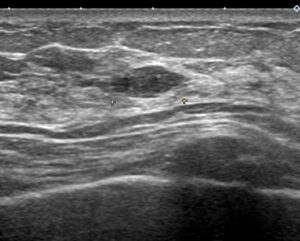

これが、当院受診時のエコー画像

やはり不整型 文句なしの「私cat.6」となります。